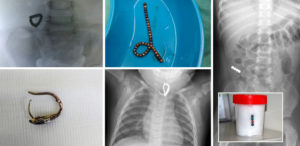

Чаще всего дети глотают детали конструктора, потом с большим отрывом идут канцелярские предметы, пуговицы, монеты, магниты, гайки, винты, гвозди.

Особую опасность представляют магниты. Если ребёнок проглотит несколько штук, они могут сгруппироваться и повредить кишечник. Ждать, что проглоченный магнит (да и любой другой предмет) самостоятельно выйдет через кишечник, не стоит. Всегда нужно обращаться к врачу.

- Любые батарейки (хоть пальчиковые, хоть мини, хоть так называемые таблетки).

- Магниты. 1 магнит, в принципе, безопасен. Но 2 или даже более представляют большую опасность. Даже сепсис может развиться из-за этого.

- Монетки. Особенно достоинством в 5 или 10 рублей. Так что ребенок проглотил 5 рублей, то в основной части случаев следует обратиться к врачу

«Самое страшное – это когда ребенок глотает батарейку, острые предметы или стекло, – говорит врач. — В первом случае это грозит химическим ожогом слизистой, во втором ее повреждениями и воспалением. — Монетки, магнитики, разные металлические предметы тоже требуют наблюдения.

Особенно если в желудок попало сразу два-три магнита (такие случаи стали частыми после того, как в моду вошел магнитный конструктор с маленькими шариками). Если же малыш проглотил резиновую кнопку, кусочек ткани, пластиковую пуговицу, детальку конструктора, целлофан – это, конечно, неприятно, но не опасно.